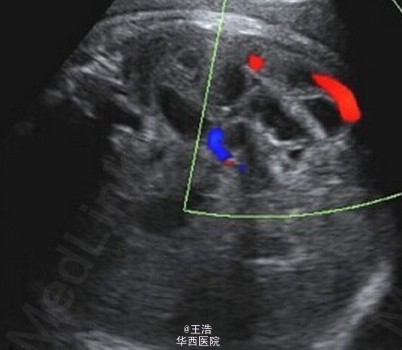

一名 35 岁初产妇,孕龄到达 30 周时出现了宫缩征象,但没有显示胎儿窘迫。超声显示胎儿发育,多普勒指数,羊水均正常。发现强回声的肠管轻度扩张,但不伴有形态学异常。病原体(TORCH)筛查阴性。第二天检查发现肠扩张伴有高回声点推断发生了进展并出现腹水,因此怀疑肠穿孔和胎粪性腹膜炎。 于是对产妇进行了紧急剖腹产。剖出一名男婴,重 2620g,在第 5 分钟及第 10 分钟 Apgar 得分都是 9 分。新生儿呼吸不稳定,腹部重度膨胀水肿呈铁青色,腹膜炎。对新生儿进行了紧急剖腹手术。术中发现证实了接生前的的诊断。切除了 50cm 坏死的回肠,且必要的实施了肠造口术。Takacs ZF, Meier CM, Solomayer EF, Gortner L, Meyberg-Solomayer G. 2014. Prenatal diagnosis and management of an intestinal volvulus with meconium ileus and peritonitis. Arch Gynecol Obstet. 290(2): 385-7.